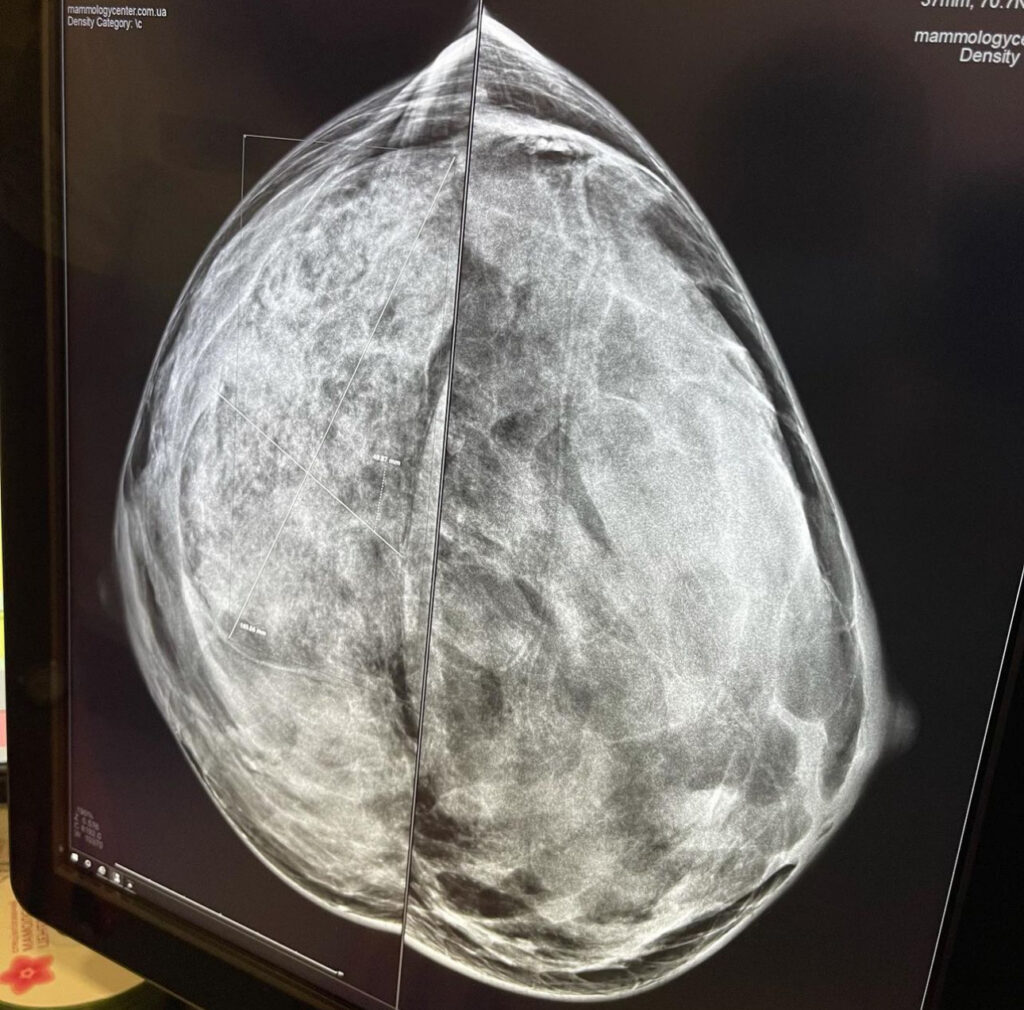

Как проводится маммография и почему не стоит ее бояться

Процедура маммографии проводится на специальном аппарате. Для этого женщине необходимо будет раздеться до пояса, сняв любые цепочки с шеи. После вас попросят задержать дыхание на несколько секунд, пока аппарат сделает снимок груди.

Единственное неприятное ощущение, которое вы можете испытать во время проведения процедуры, – это легкое сдавливающее чувство, когда вашу грудь будет прижимать специальная пластина. В результате обследования врач получит снимок, на основании которого и будет поставлен будущий диагноз.